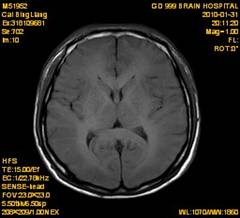

案例2 患者,女,30岁,二氯乙烷中毒性脑病的头颅MR。表现为双侧大脑半球皮层下白质、双侧外囊、双侧苍白球及双侧小脑齿状核内广泛片状、斑片状长T1长T2异常信号影,FLAIR序列呈高信号,增强后病变未见明显强化。

给予抗炎、脱水、疏通血管及营养神经等药物治疗。经过40天的对症治疗,痊愈出院。